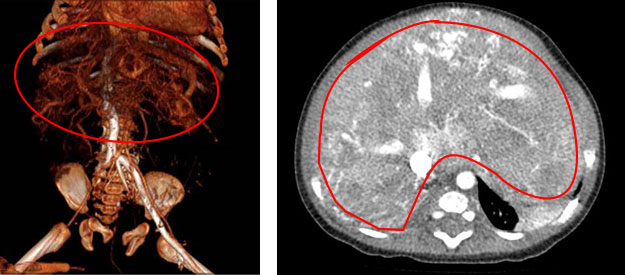

一边积极维持血流动力学稳定,一边积极跟家长沟通病情,并做好术前准备。次日张靖主任主导手术。术中见肝脏多发血管瘤及多发肝动静脉瘘形成,术中给予肝动脉栓塞,再次造影显示动静脉瘘明显减少,手术过程非常顺利。

肝脏CT三维重建影像 肝脏CT显示巨大肝脏及多发病灶